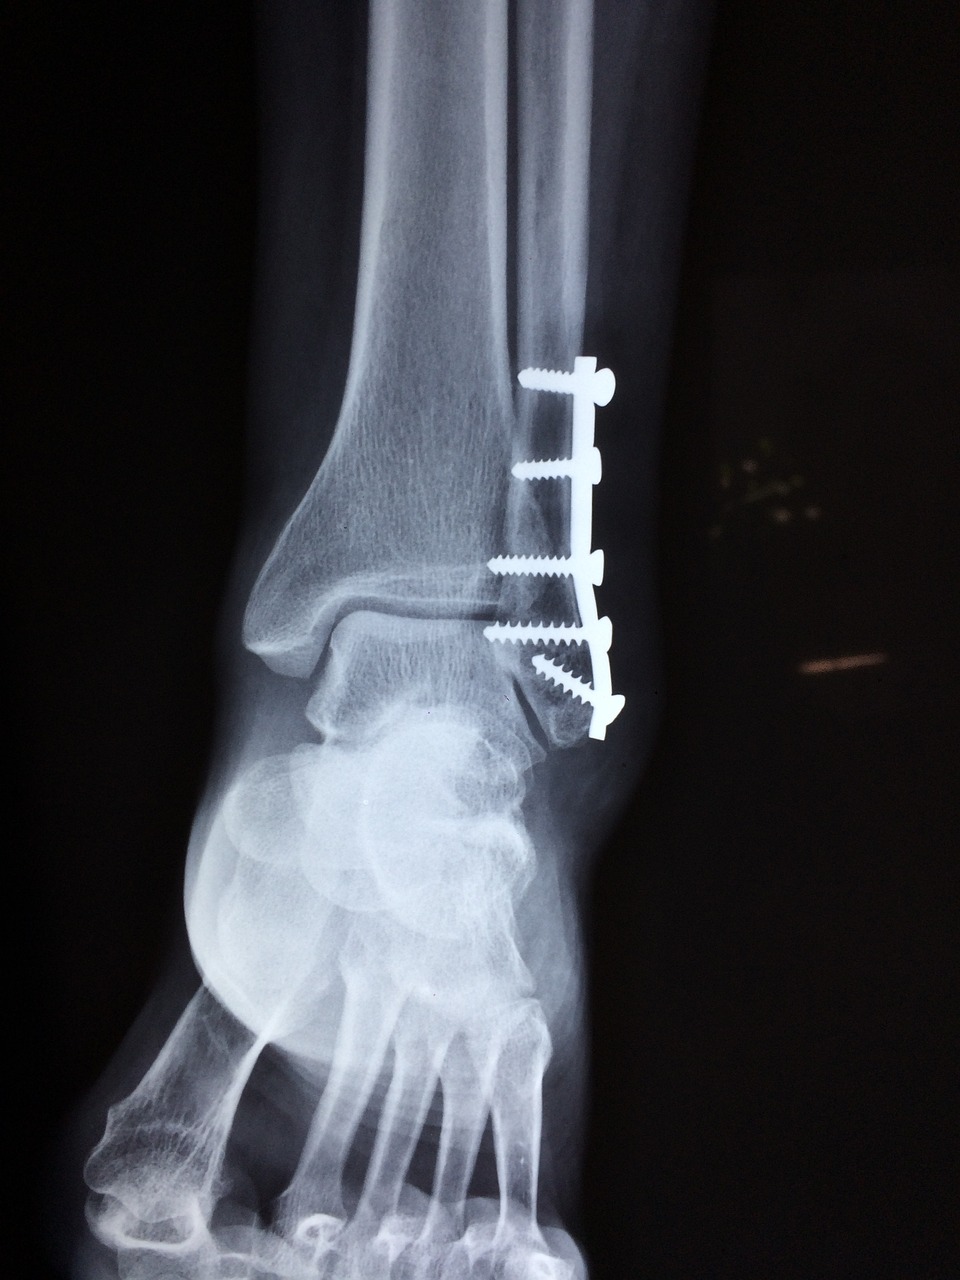

골절 환자를 돌보는 거, 엄청 섬세하고 머리 좀 써야 하는 일이죠? 우리가 알아둬야 할 기본적인 것들이 몇 가지 있어요. 첫 번째로, 골절된 부위를 딱 맞게 평가해서 안정시키는 게 중요해요. 이거 하나만 제대로 해도 다른 손상 막고 아픔 줄일 수 있으니까요.

골절 간호기술이란 건 환자가 얼른 나을 수 있게 해주는 필수템이에요. 제대로 된 간호 기술로 골절 부위를 계속 체크하고 잘 돌봐줘야 해요. 간호사님이 붓기나 색깔 변화, 이상한 느낌, 혈액 순환이 잘 안 되는 문제 같은 걸 꼼꼼히 보셔야 하잖아요.

그리고 우리 간호사님들, 골절 후 나타날 수 있는 합병증도 찾아내고 막는 게 엄청 중요해요. 예를 들어서 욕창이나 혈전 같은 문제들 말이죠. 제대로 된 간호와 주의로 이런 걸 예방할 수 있다니까 신경 써주세요! 이런 합병증들 때문에 회복 시간만 길어지고, 심하면 생명 위협받을 수도 있으니까 말이에요.